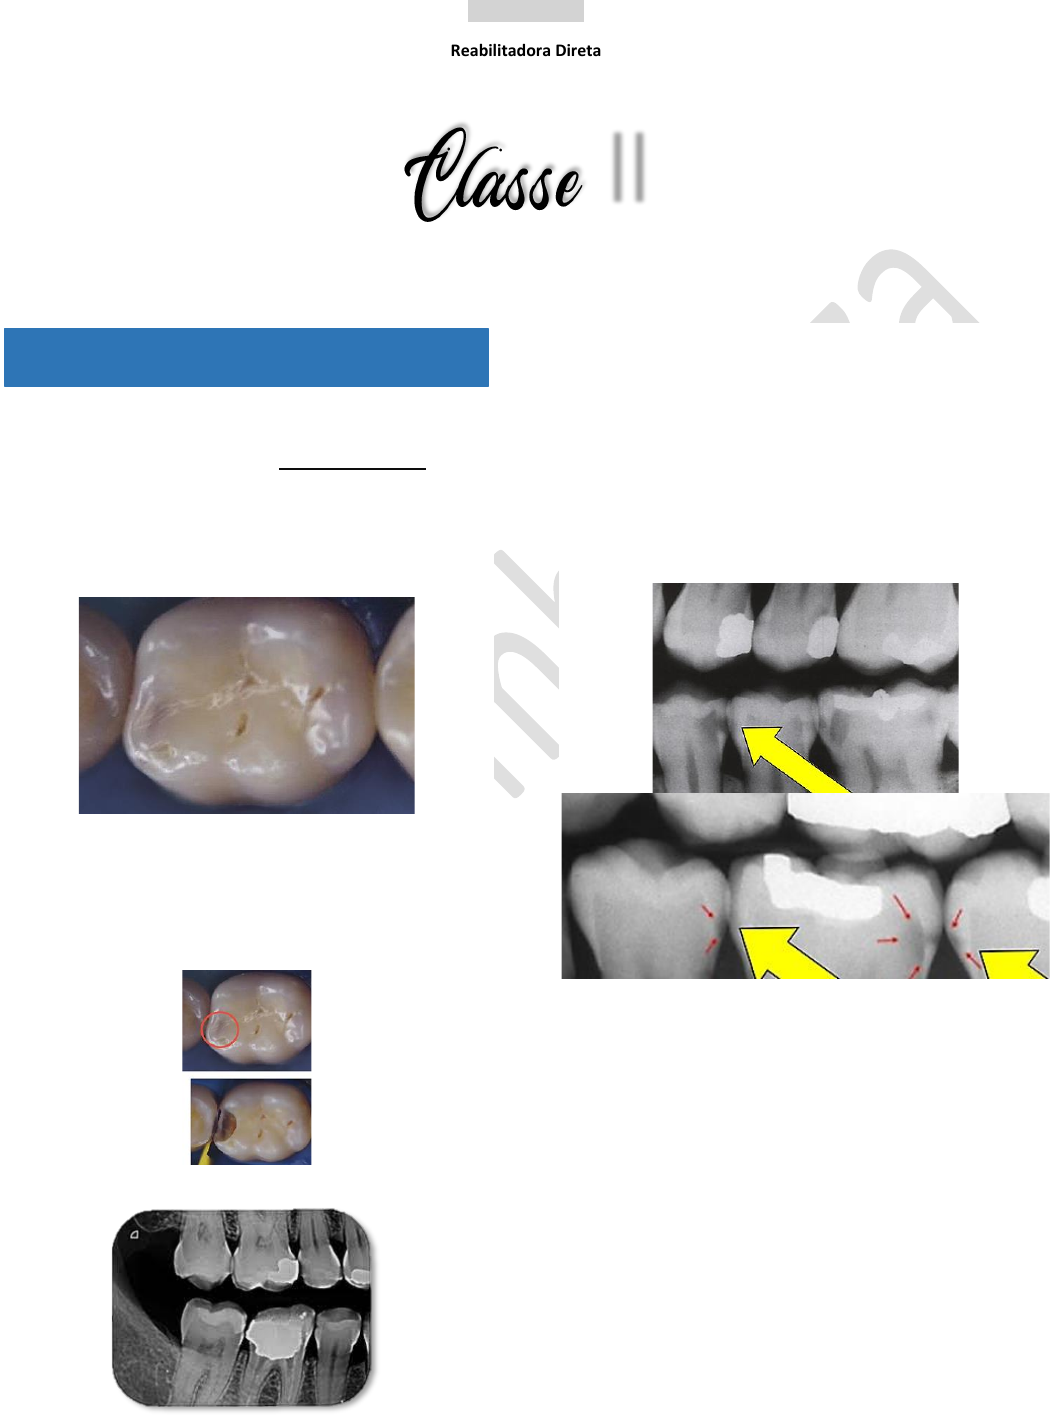

CLASSE II—Localização

• Superfícies lisas;

• Proximais de dentes posteriores;

↳ cárie oculta em face proximal; tom escurecido.

↳ avaliação composta por análise clínica visível +

exame radiográfico complementar.

EXAME COMPLEMENTAR

✓ Radiografia Inter-proximal;

✓ Radiopaco: claro.

✓ Radiolúcido: escuro.